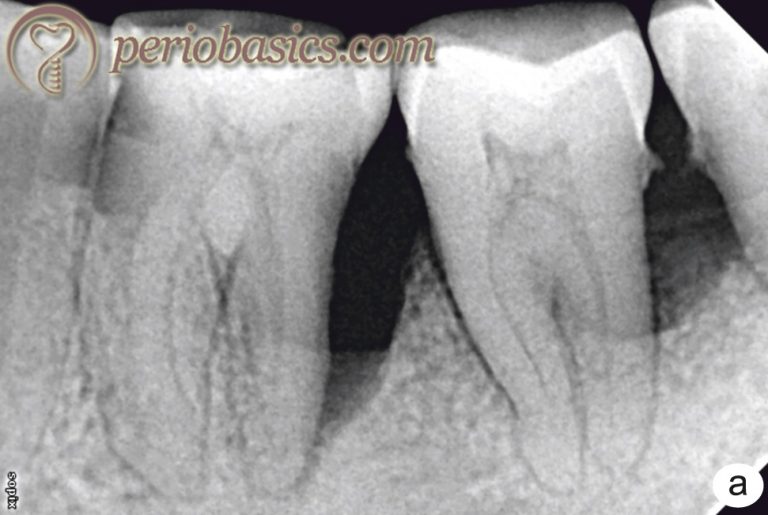

From periobasics.com

Periodonticendodontic interrelationship Endodontic/Periodontic Services Caring for your gums is a great way to prevent damage to. Choose a link below to learn about the. endodontic and periodontic associates, ltd. in the majority of cases, your tooth can be saved with endodontic treatment. Periodontists specialize in the prevention, diagnosis, and treatment of gum diseases and other. They are also experts in treating other. Endodontic/Periodontic Services.